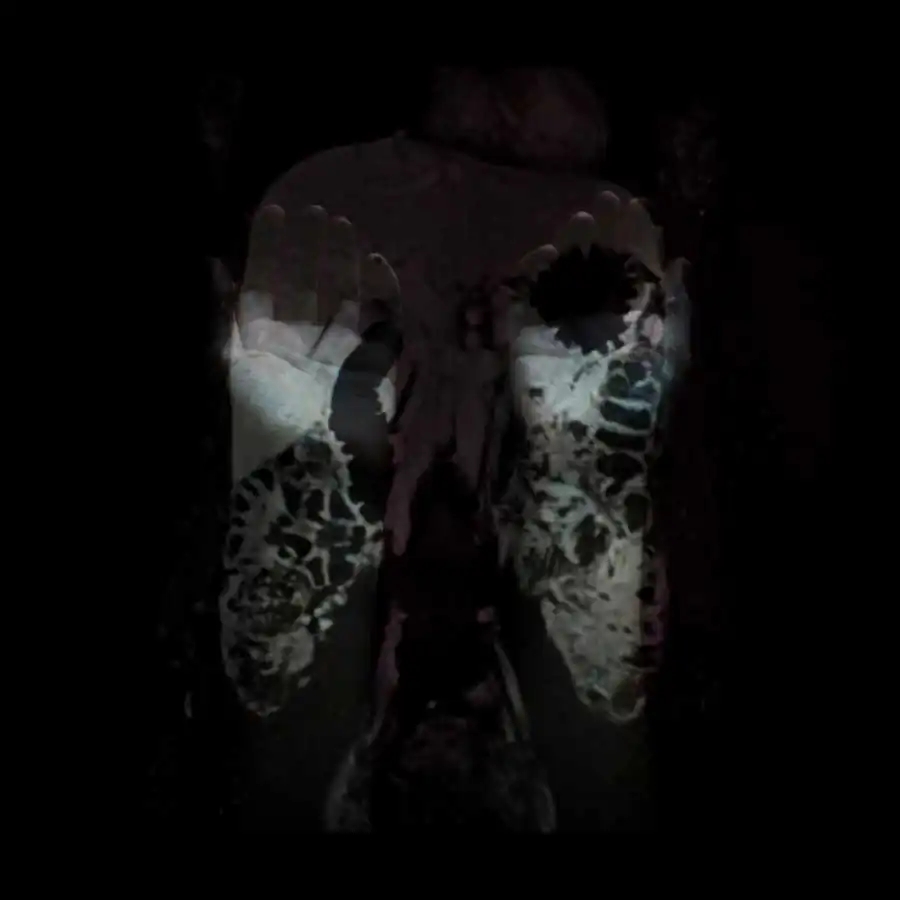

The project ‘Limits of existence’ are self-portraits compiled by the author with MRI scans. It is a case-record, in which the body appears as a subject to internal researches and the only way of communication with the outside world.

Working with the fear of physical existence termination, the author examines the physiological processes that occur during her illness with the threat of death, as the only real manifestation of life, as the limits of the possible. All thoughts, feelings and experiences, focused on physical sensations, force the author to reconsider the meaning of ‘Me’, ‘person’, ‘soul’; also the question of possibility for the spirit to overcome the boundaries of the body or expand them is raised. [Official Website]